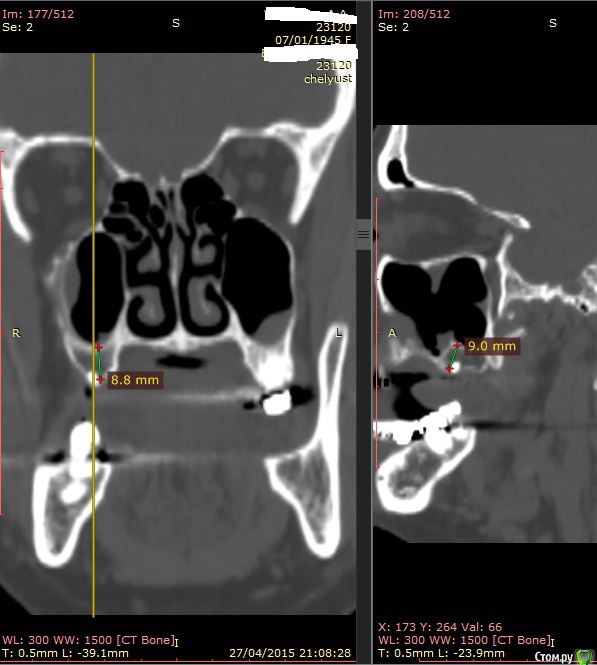

Alexey Doc Опубликовано 29 апреля, 2015 Поделиться Опубликовано 29 апреля, 2015 В клинику с целью протезирования обратилась пациентка 70 лет.Ортопед направил на консультацию. В анамнезе: со слов больной год назад удален зуб 1.6 после чего сформировался оро-антральный свищ. В январе 2015 года выполнена правосторонняя радикальная гайморотомия с удалением 1.5, 1.7 зубов. Сопутствующая патология в стадии компенсации.На сегоднещний день жалоб кроме отсутствия зубов нет.В полости рта : верхний свод преддверия справа плавно перетекает в небо мощным тяжем подвижной слизистой шириной примерно 15-17 мм . Альвеолярный отросток отсутствует. Какой\ие минимально инвазивные( учитывая возраст пациентки) способы аугментации вы бы применили у этой больной для последующего протезирования с опорой на имплантатах? Буду рад любому мнению и рац.предложению.Ниже свежие срезы КТ. Ссылка на комментарий

Alexey Doc Опубликовано 30 апреля, 2015 Автор Поделиться Опубликовано 30 апреля, 2015 Бабуля может еще 30 проживет...Я за зигомыЗигомами не владею.Вот еще пара картинок реконструкции Ссылка на комментарий